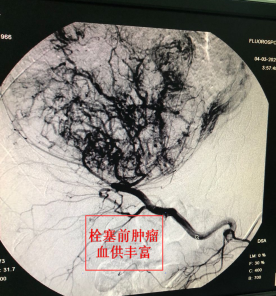

检查显示,患者肝右叶约有12cm占位、肝静脉栓子形成,确诊为肝癌晚期,无法手术切除病灶。肿瘤血液科室组织医疗组会诊后,结合患者病情,最后拟定了采用TACE治疗方法。

TACE技术即经导管肝内动脉栓塞化疗术,是将导管选择性或超选择性插入到肿瘤供血靶动脉后,以适当的速度注入适量的栓塞剂,使靶动脉闭塞,引起肿瘤组织的缺血坏死。该方法在市第一人民医院已成功开展多年,也是近年来广泛开展的一种治疗原发性肝癌的方法,具有安全、有效、微创、风险低等优点,被认为是治疗不可手术切除的中晚期肝癌的首选方法。多用于肝动脉插管化疗栓塞,或肝动脉插管化疗灌注等肝癌治疗。

据肿瘤血液科副主任医师孙铭强介绍,TACE技术是经肿瘤供血动脉灌注化疗药物,进行区域性化疗,与全身静脉给药相比,药物浓度更高(局部给药约大于全身给药浓度的200倍以上),具有不开刀、效果好、疗效快、副作用小的优点;该方法使用抗癌药物或药物联合微粒、微球进行栓塞,既可切断血供,导致肿瘤缺血、缺氧,又可以缓慢释放抗癌药物,达到抑制肿瘤生长,促使肿瘤细胞坏死、凋亡的目的。

通过与患者家属充分沟通并征得同意后,肿瘤血液科于3月4日成功为患者实施TACE治疗。仅在大腿根部皮肤上穿刺3~5毫米的小口,经股动脉插管至肝癌供血动脉,采用局部靶向药物灌注及栓塞肿瘤供血血管的方式集中杀灭肿瘤细胞。